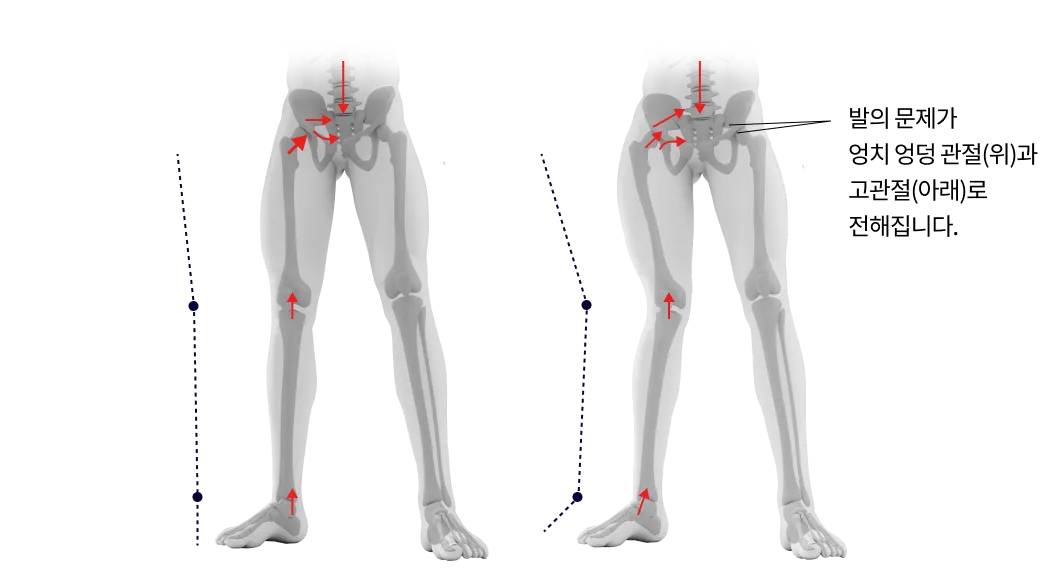

발의 문제는 전신통증의 시작입니다.

발은 우리 몸에서 건물의 주춧돌과 같은 역할을 합니다. 발의 틀어짐으로 인한 통증은 단순히 발의 문제로 그치지 않고 보행 패턴을 무너뜨리며 다리와 무릎 관절, 나아가 골반과 허리의 추간판까지 연쇄적인 영향을 미칩니다. 발의 문제를 조기에 발견해 치료하는 것이 전신 건강을 위해 중요합니다.

▲ 발의 문제로 인해 생기는 요통